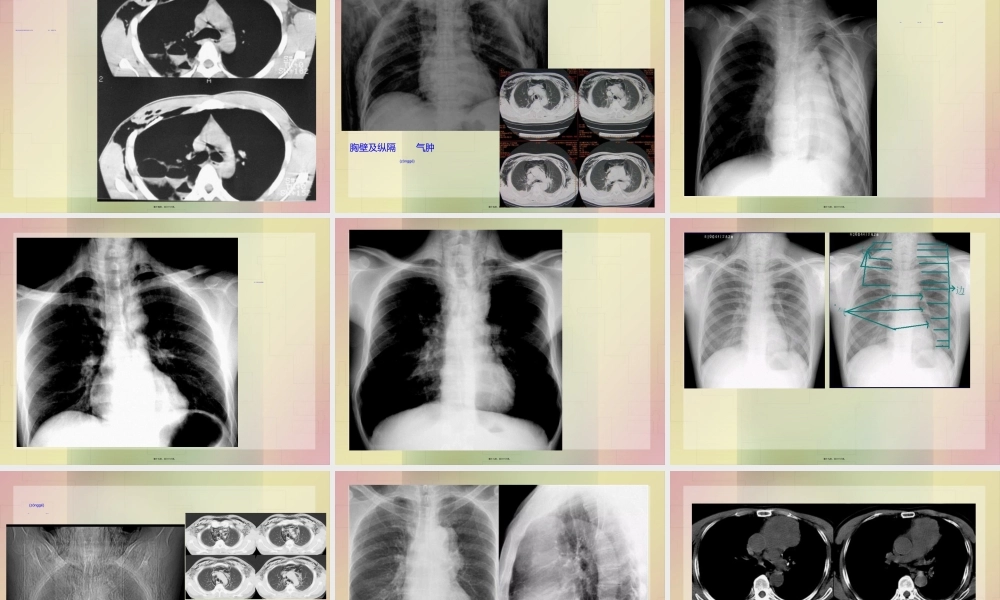

胸部胸部(xiōnɡbù)(xiōnɡbù)外外伤伤第一页,共六十六页。病理(bìnglǐ)与临床•肋骨骨折比较常见(chánɡjiàn),可为单发骨折,也可为多发骨折,还可为单一肋骨的多处骨折。以3-10肋的腋部及背部多见。第二页,共六十六页。病理(bìnglǐ)与临床第三页,共六十六页。病理(bìnglǐ)与临床第四页,共六十六页。X线表现(biǎoxiàn)1.肋骨骨折本身第五页,共六十六页。X线表现(biǎoxiàn)肺挫伤第六页,共六十六页。X线表现(biǎoxiàn)1.纵隔气肿表现为纵隔两旁(liǎngpáng)平行于纵隔的气带样影。第七页,共六十六页。•第八页,共六十六页。•左下肺创伤性湿肺,左侧胸壁皮下气肿。第九页,共六十六页。•两侧胸壁皮下气肿第十页,共六十六页。•左侧胸部术后,胸壁皮下气肿形成第十一页,共六十六页。(jǐnɡbù)第十二页,共六十六页。患者男,37岁,外伤后右侧胸痛1天(被锚挤压伤)。患者除胸痛外,无咳嗽、咯血。患者否认“既往肺部疾病史”。第十三页,共六十六页。影像所见结合病史诊断右肺撕裂伤及肺血肿(肺气囊形成),右胸壁皮下气肿。第十四页,共六十六页。胸壁及纵隔(zònggé)气肿第十五页,共六十六页。•纵隔气肿。纵隔内见带状低密度影第十六页,共六十六页。纵隔气肿。气管旁见带状低密度影第十七页,共六十六页。•纵隔气肿上纵隔气管(qìguǎn)两旁均见带状低密度影第十八页,共六十六页。第十九页,共六十六页。纵隔(zònggé)及皮下气肿横膈连续(liánxù)征第二十页,共六十六页。第二十一页,共六十六页。第二十二页,共六十六页。肺血液循环肺血液循环(xuèyèxúnhuán)(xuèyèxúnhuán)障碍障碍性疾病性疾病肺水肿肺栓塞第二十三页,共六十六页。肺水肿的病理(bìnglǐ)与临床•肺水肿是肺部血管外液体的增多,过多的液体积聚在肺间质和终末气腔内。根据肺水肿的发生机制,临床分为以下几类:①毛细血管(máoxìxuèɡuǎn)内静水压升高引起的肺水肿,如心源性肺水肿;②毛细血管(máoxìxuèɡuǎn)通透性增高引起的肺水肿;③其他原因如复张后肺水肿,高原性肺水肿等。第二十四页,共六十六页。X线表现(biǎoxiàn)1.间质型肺水肿•⑴肺血重新分布:两肺上野比下野的血管阴影粗。第二十五页,共六十六页。X线表现(biǎoxiàn)2.肺泡型肺水肿第二十六页,共六十六页。(dàpiàn)第二十七页,共六十六页。(fèipào)第二十八页,共六十六页。•肺泡(fèipào)性肺水肿第二十九页,共六十六页。(zhō...